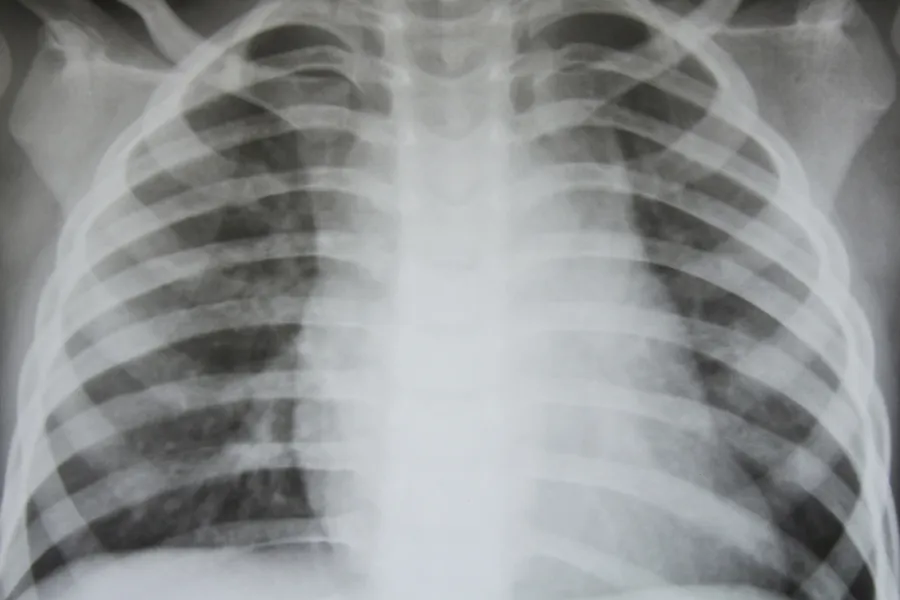

Mangelfulle røntgen-rekvisisjoner skaper forsinkelser

Mange rekvisisjoner mangler nødvendig informasjon og feiler på veien til mottaker. De havner i en errormappe og blir ikke lest inn i fagsystemet til røntgen.